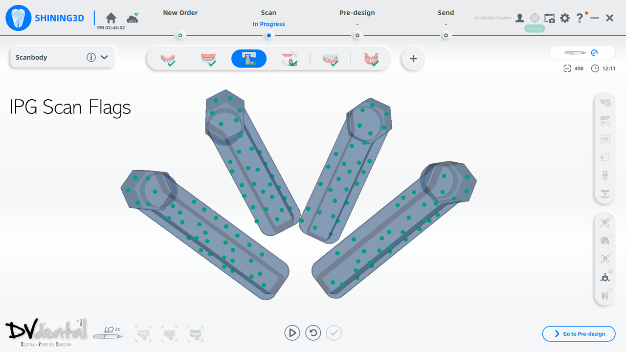

In this case, we encountered a problem: while the MUA of the four anterior implants were compatible with the IPG scan bodies, the two posterior implants were not compatible with the IPG scan bodies. Therefore, we will scan the two posterior implants using normal 3D reconstruction technology (in the soft tissue scan, placing two standard scan bodies on the MUA of the two posterior implants) and then scan the anterior implants with IPG technology (placing the IPG scan bodies on the MUA of the four anterior implants).

In the next stage, alignment between the IPG scan bodies and the soft tissue, along with the standard scan bodies, will be performed to obtain a digital model with six scan bodies of the Implants.

Fig 7: In the same arch, four MUAs are coded scanbody compatible, while the rest two MUAs are coded scanbody non compatible.

Fig 11,12: Step 6, install and scan the coded scanbody using photogrammetry technology